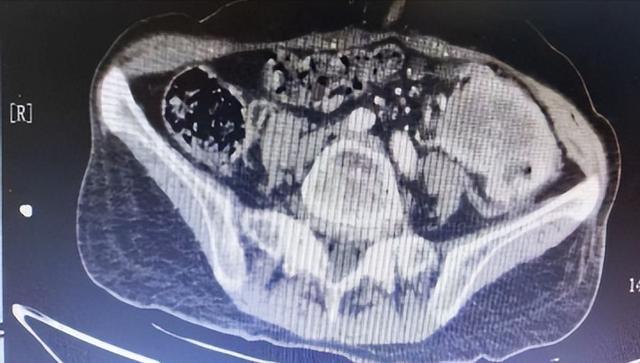

(▲2025年9月8日初诊胸部及全腹部增强CT:肿瘤病灶大小65*47mm,肠壁增厚约30mm,肠腔狭窄,周围间隙模糊等。)

为进一步治疗入住肿瘤科后,检查发现,蒋奶奶乙状结肠呈肿块样增厚,同时伴随右肾、肝脏多处结节,肿瘤病灶大小达65*47mm,肠壁增厚约30mm,肠腔狭窄明显,晚期结肠癌诊断明确。